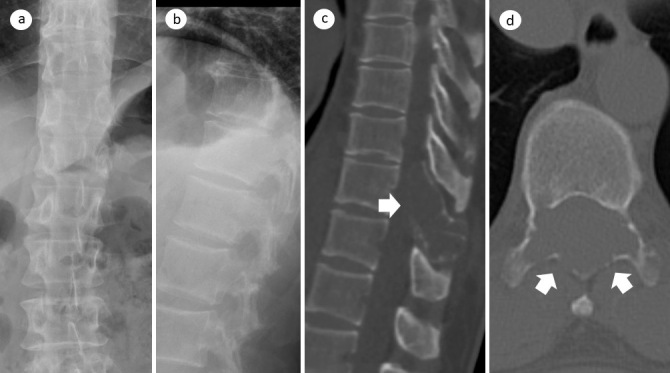

A Case of Desmoplastic Fibroma of the Thoracic Spine with Incomplete Paralysis of both Lower Limbs.

胸椎结缔组织增生纤维瘤伴双下肢不完全瘫痪1例。